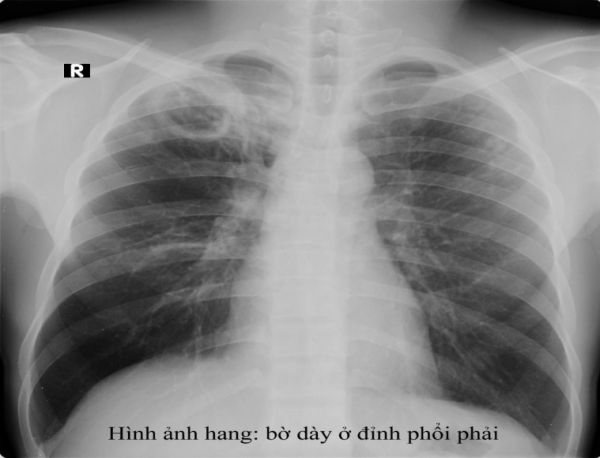

Lao hang phổi phải có mức nước mức hơi

Lao hang phổi phải có mức nước mức hơi trên phim chụp x quang ngực. Để hiểu rõ hơn về bệnh lý này mời các bạn cùng tham khảo bài viết ngay dưới đây nhé!

Trên đây là một số thông tin và hình ảnh về Lao hang phổi phải có mức nước mức hơi, hy vọng sẽ giúp các bạn có được những hiểu biết về bệnh để có hướng điều trị phù hợp và hiệu quả!